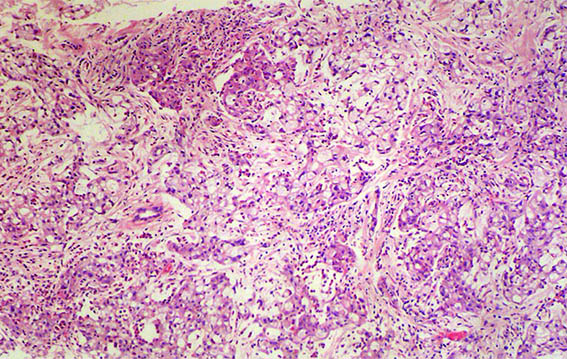

Figura 2. H&E, X100.